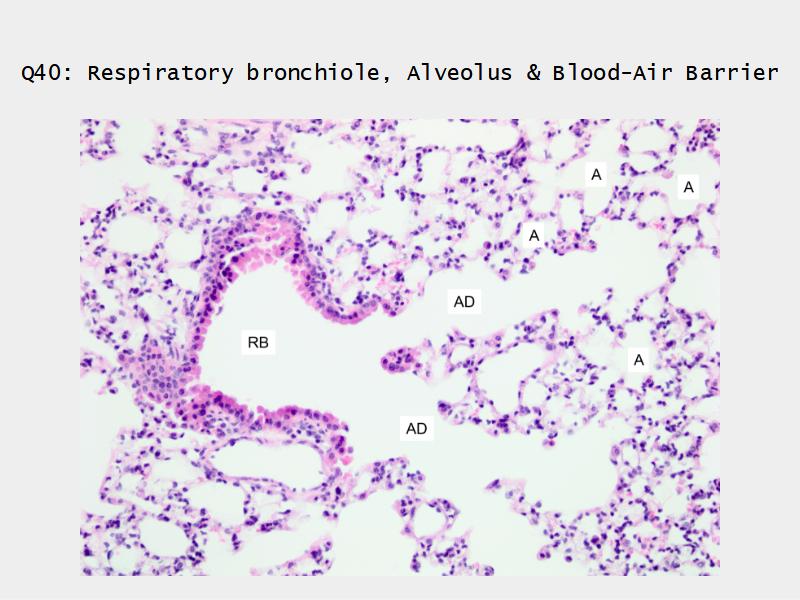

- Respiratory bronchioles

- Conducting -> Respiratory

- Simple cuboidal epithelium

- Secretory cells

- Alveoli